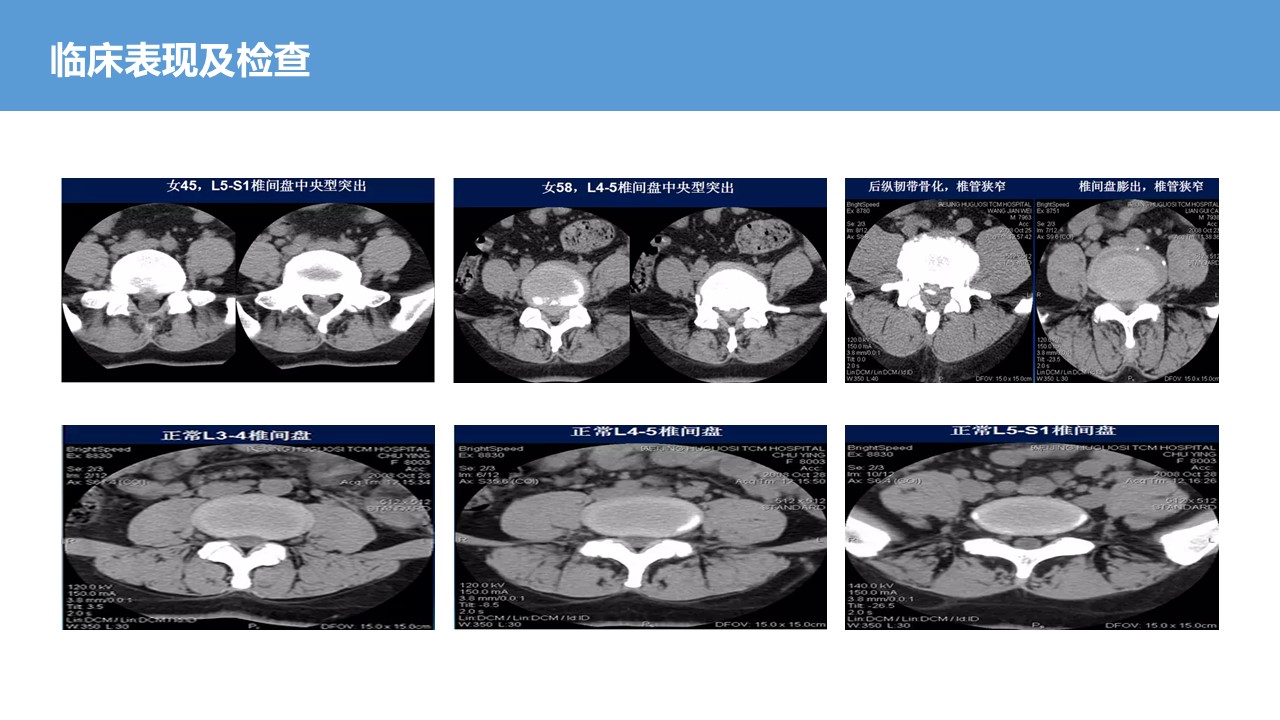

腰椎间盘突出症知识培训4